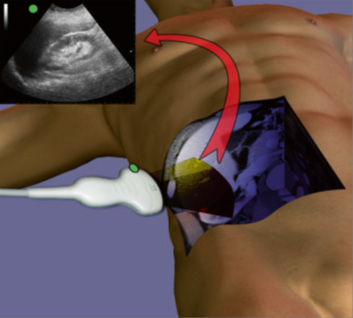

US FAST comprises four views, each one seeks to detect the presence of abnormal intra -abdominal hypoechoic free fluid, whose presence may explain the clinical condition of a patient who has suffered trauma. The 4 positions can be performed in any order, but a complete scan must include evaluation in each of them. Conventionally the display marker represents the right side, so the transducer must also be used in that position. Additional scans or views extend the basic US FAST exam and make it E – FAST. These are essentially views of the lower chest to look for signs indicating intrathoracic hemorrhage (Figure 1).

Figure 1 The 4 basic windows of the abdominal FAST exam: 1. Subxiphoid 2.

Hepatorenal 3. Renal splenus 4. Supra pubic.